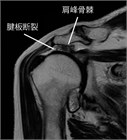

1. 肩関節の痛みの原因として、腱板断裂、石灰性腱炎、凍結肩(五十肩、肩関節周囲炎)、変形性関節症を想起すべきである(推奨度1)

1. 肩の痛みを訴える患者で、①棘上筋の筋力低下、②外旋筋の筋力低下、③インピンジメント徴候、の3つがそろっていれば98%の確率で腱板断裂と診断できる(推奨度2)